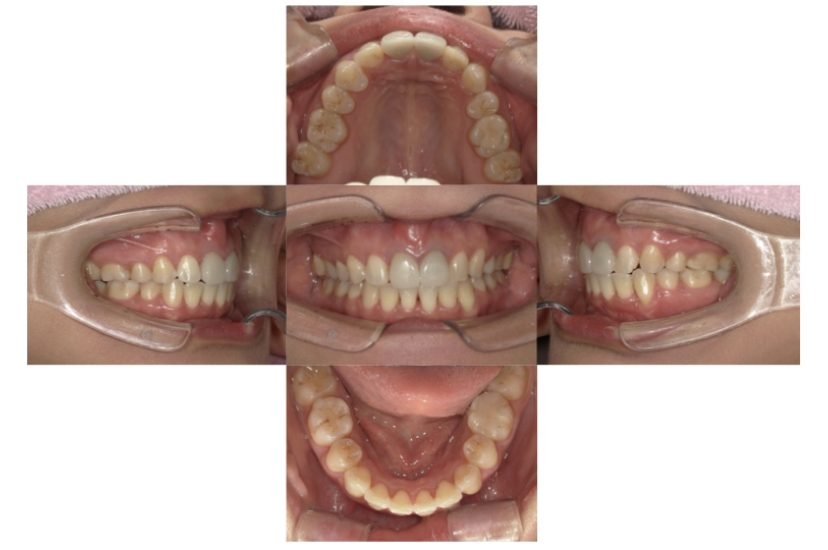

症例3

叢生

抜歯

ブラケット矯正

上下顎叢生(上下の前歯のガタガタ)のケースです。

装置はラビアル(上下表側)で、上下顎の小臼歯を4本抜歯を行っています。抜歯したスペースを使って、上下の前歯の後方移動と叢生(ガタガタ)の改善を行っています。

主訴 八重歯を治したい。

年齢・性別 25歳 女性

お住まいの地域 神奈川県川崎市

治療方針 抜歯スペースを利用して上前歯の叢生(ガタガタ)の改善

抜歯部位 上下顎左右第一小臼歯

使用装置 ラビアル(上下表側)、顎間ゴム

治療期間 1年11か月

治療回数 16回

リテーナー クリアリテーナー

BEFORE

AFTER